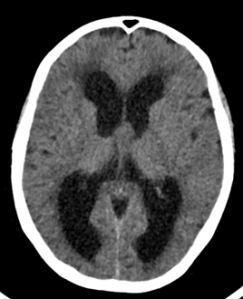

Se trata de un paciente de 63 años que comienza de forma subaguda con torpeza a la marcha y urgencia e incontinencia miccional. Acudió al servicio de urgencias donde se le realizó una TAC cerebral sin contraste (imagen 1 y 2) donde se observaba una hidrocefalia y se derivó a estudio ambulatorio con la sospecha de hidrocefalia normotensiva (imagen 2). La hidrocefalia se produce como consecuencia del aumento del líquido cefalorraquideo en el sistema ventricular cerebral o el espacio subaracnoideo.